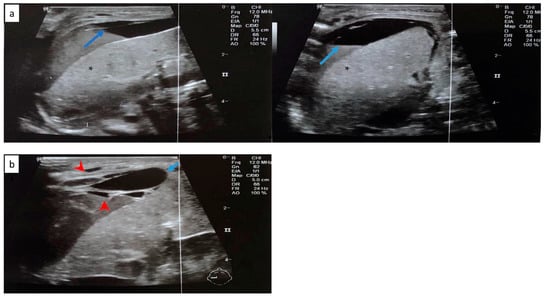

Cranial ultrasound revealed a 1st-degree IVH. Abdominal ultrasound revealed free perihepatic, perisplenic, and inter-intestinal fluid collection (Figure 5a). Abdominal distension was noted in the radiography (Figure 6).

Figure 5.

(a) Free perihepatic fluid collection (blue arrow) in abdominal ultrasound. (b) Abdominal ultrasound depicting subcapsular hematoma of the liver (blue arrow) and hemorrhagic collections in the peritoneal cavity (red arrowhead). Normal liver parenchyma is noted with asterisk (*).

The following day, the clinical condition of the neonate deteriorated, with persistent hypotension, edema and without urine output. A second abdominal ultrasonography revealed subcapsular hematoma of the liver and the spleen and hemorrhagic collections in the peritoneal cavity (Figure 5b). The blood cultures and peritoneal fluid cultures grew Klebsiella pneumoniae. Despite the supportive treatment, the neonate worsened dramatically and deceased on the 8th day.

The neonate was then stabilized, and ultrasonography was performed in order to differentiate the possible causes of blood loss. No IVH was confirmed by cranial ultrasonography, while abdominal ultrasonography depicted a hypoechogenic intrahepatic irregular lesion on the right lobe (3.4 cm × 1 cm) (Figure 8a), with hematoma being the possible diagnosis from the radiologist. Chest and abdominal radiography (Figure 9a) showed an abnormal position of UVC, so it was removed. On the following radiography (Figure 9b) air in the branches of right portal vein and hepatic parenchyma was noted (as shown in Figure 9b).

Figure 8.

(a) Abdominal ultrasonography depicting hypoechogenic intrahepatic irregular lesion on the right lobe (3.4 cm × 1 cm) (blue arrow); and (b) abdominal ultrasonography depicting the calcific deposits (1 cm × 1 cm) (blue arrow) at the right lobe of the liver. Normal liver parenchyma is noted with asterisk (*).

The following days the neonate remained hemodynamically stable, with no evidence of new blood loss throughout the rest of her stay in the NICU. Subsequent abdominal ultrasound showed a gradual resolution of the intrahepatic lesion. Three months after the initial scan, at the right lobe of the liver, multiple hepatic calcific deposits (1 cm × 1 cm) were demonstrated (Figure 8b). The infant was discharged home on the 72nd day of life. To this date, she remains well, albeit the sequelae of his prematurity.